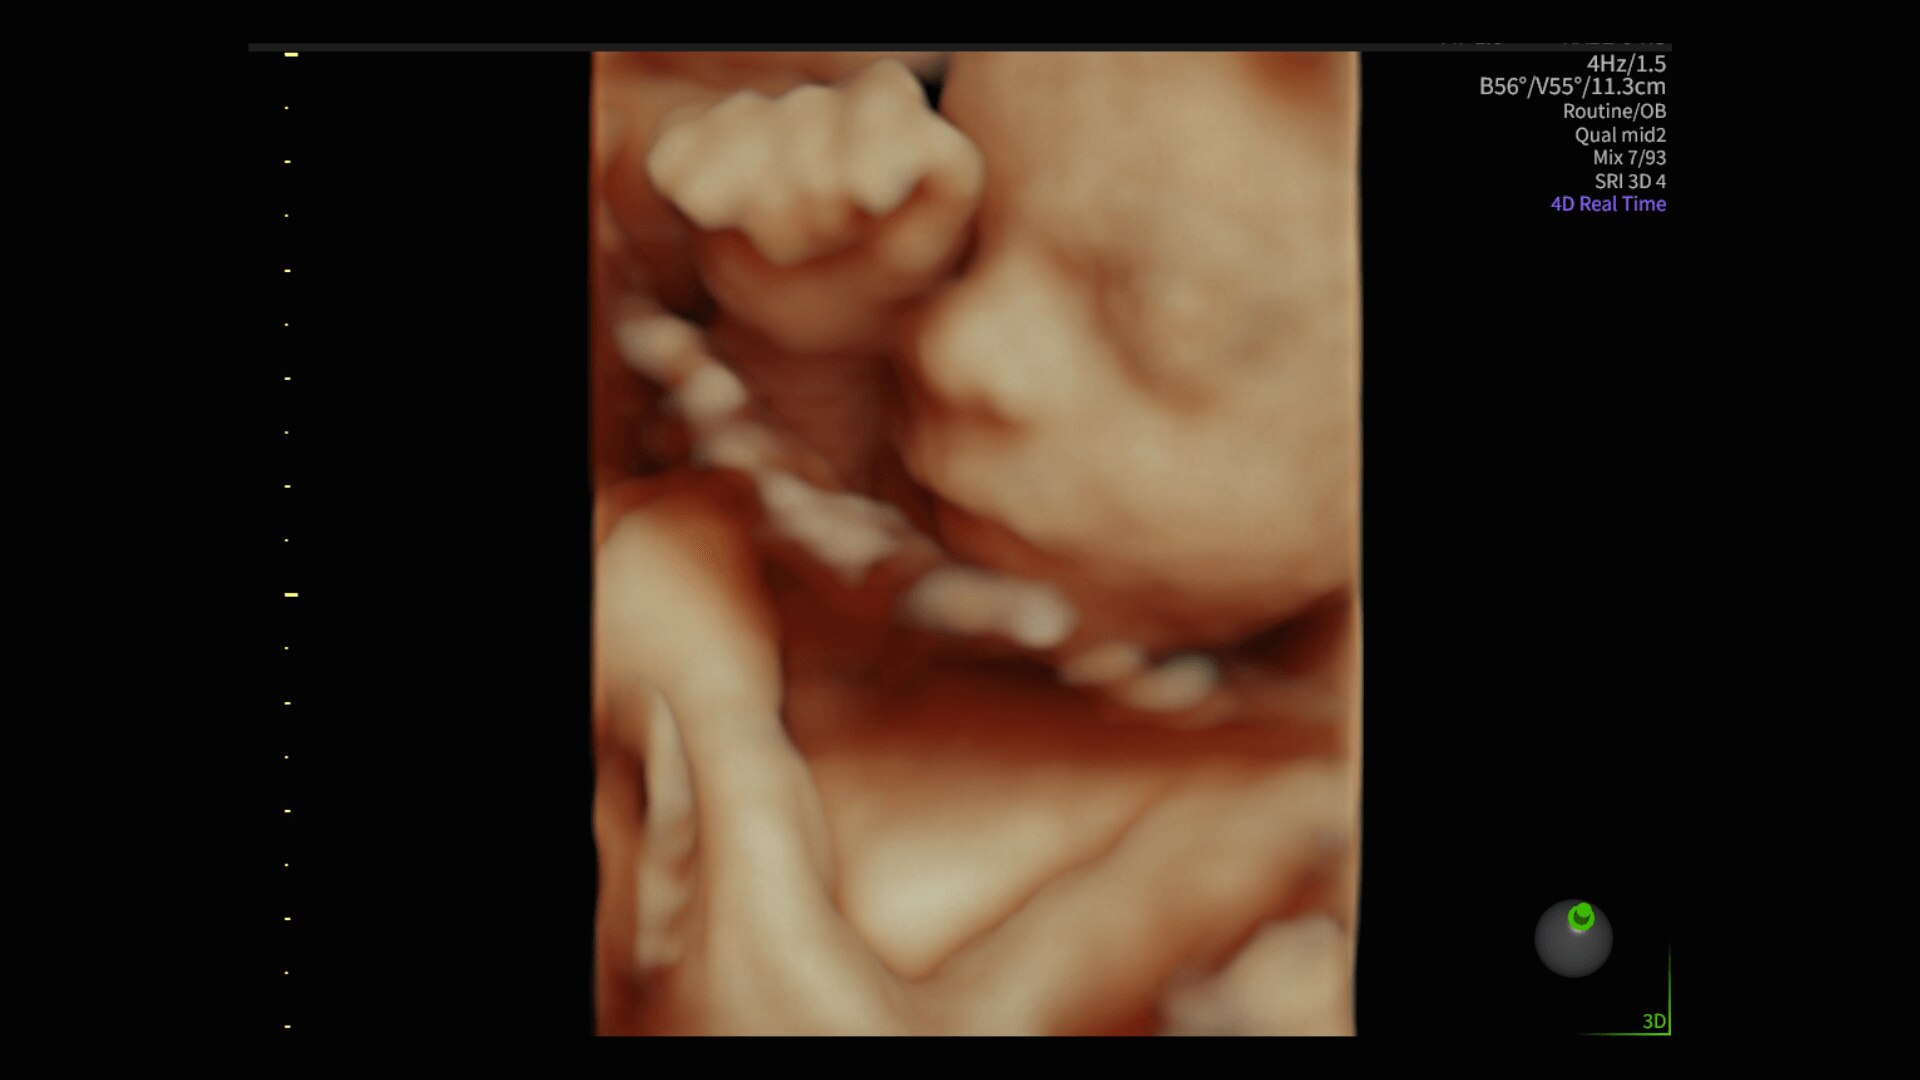

Image quality

Excellent images that are easy to acquire

Image quality is everything in ultrasound

The Voluson Performance 18 delivers high-resolution, detailed imaging with one-touch optimization for effortless scanning—helping you deliver quick, confident answers across a wide range of patient.